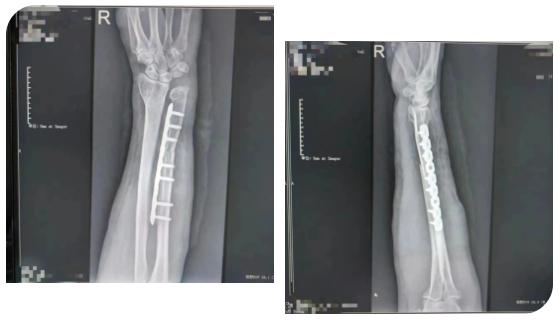

患者于门诊善相关检查后诊断为:右侧尺骨撞击综合征。创伤外科主任医师王磊及其团队在仔细评估后,经过周密的术前准备,在臂丛麻醉下行“右侧尺骨短缩截骨”。该术式通过恢复中立或负向的尺骨变异来解压尺腕关节从而缓解尺骨撞击症状。

术后患者右腕关节疼痛明显缓解,活动度增加,功能得到了很大改善。